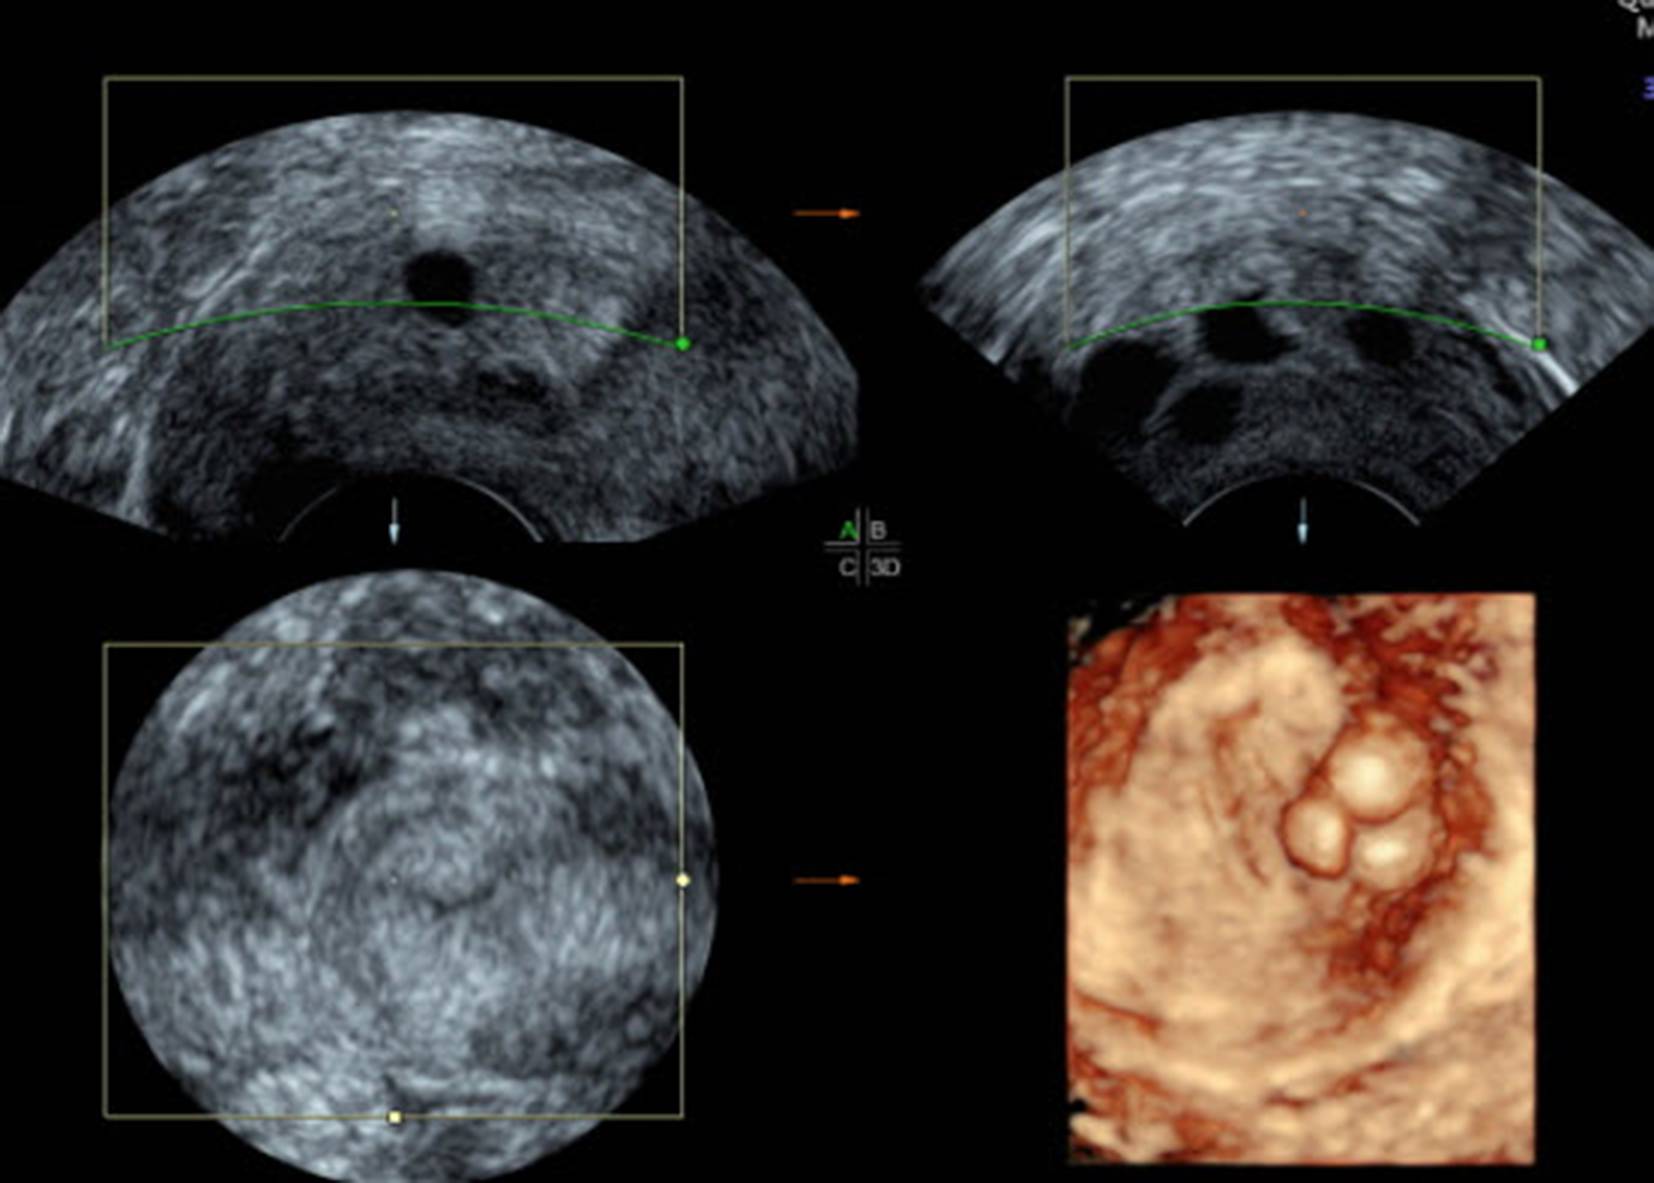

Ovula Nabothii liegen oft unmittelbar dem Portioepithel an, manchmal liegen sie auch „höher“, bis zum Bereich des unteren Uterinsegments (Abb. 1). Da Ovula Nabothii einen echoarmen Inhalt haben, beobachten wir oft unmittelbar dahinter eine dorsale (distale) Schallverstärkung (Abb. 2). Schallverstärkung wird in manchen Anwendungsbereichen des Ultraschalls (Gallenblasendiagnostik, Mammasonografie) als diagnostisches Kriterium bei der Beurteilung von zystischen Strukturen herangezogen. Die erhöhte Echodensität hinter dem Ovulum Nabothii muss als Schallartefakt erkannt werden und darf nicht als Strukturverdichtung des Zervixgewebes interpretiert werden (Abb. 3). Ovula Nabothii sind selten bei nulliparen Frauen, sie treten nach Geburten, Operationen an der Zervix, wie z. B. der Versorgung von Emmet-Rissen, oder auch nach Konisationen auf. Ovula Nabothii können platzen und der Inhalt ausrinnen, in diesem Bereich können sich neue Zysten, aber auch echodense Narbenstränge bilden. Im Ultraschall sind Ovula Nabothii ein gutes Einsatzgebiet für den 3D-Schall: Dieser, hilft die Zyste besser zu lokalisieren (Abb. 4, 5 und 6).

Abb. 6

Einsatz des 3D-Modus zur Darstellung von mehreren nebeneinanderliegenden Ovula Nabothii